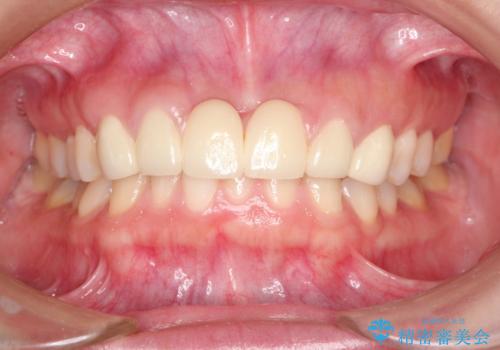

- 数ヶ月前に治療終了したブリッジの歯ぐきの違和感が強く、改善を求めて来院されました。

歯ぐきは著しく腫れ、少し触ると出血してしまうような状態であったためブリッジの再作製・歯周外科を用いた歯肉環境の改善を計画します。

- 74万円(仮歯×6・ファイバーコア×4・ジルコニアクラウン×6)費用は治療当時の料金となります